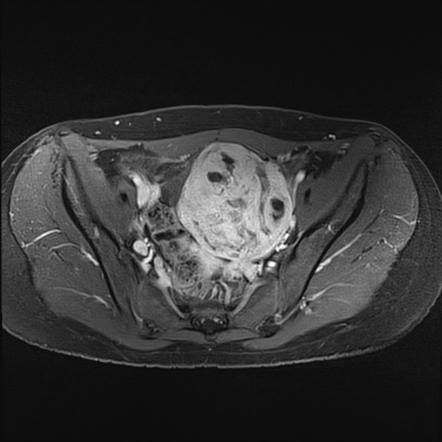

Rhabdomyosarcoma (genitourinary Tract) | Radiology Reference Article

radiopaedia.org

radiopaedia.org

rhabdomyosarcoma genitourinary radiology tract radiopaedia bladder

, 19. Rhabdomyosarcoma. (18) Axial Pelvic CT Scan Obtained With

www.researchgate.net

www.researchgate.net